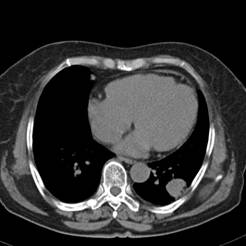

典型病例2:患者张XX,男,65岁,住院号:496686,因发热、胸闷、背痛2月余入院,体温最高达39℃,背部疼痛难忍。2015年6月29日胸部增强CT示:右肺下叶11.6cmx12.5cm巨大肿块,中心大片低密度坏死区,第8胸椎及右侧第8后肋骨转移。于7月2日行CT引导下穿刺活检术,病理证实为右肺鳞癌。给予125I放射性粒子植入治疗,术中首先利用植入针,穿刺肿块中央坏死区,连接引流袋后抽出肿瘤内坏死液体约500ml,抽液后肿瘤缩小约1/3;随后将125I粒子植入到第8胸椎体及第8后肋骨转移区,同时重点放置患侧滋养动脉供血区域。术后第二天,患者体温恢复正常;术后一周随访,患者背痛缓解。该患者出院回家,仍在随访中。

术前CT片